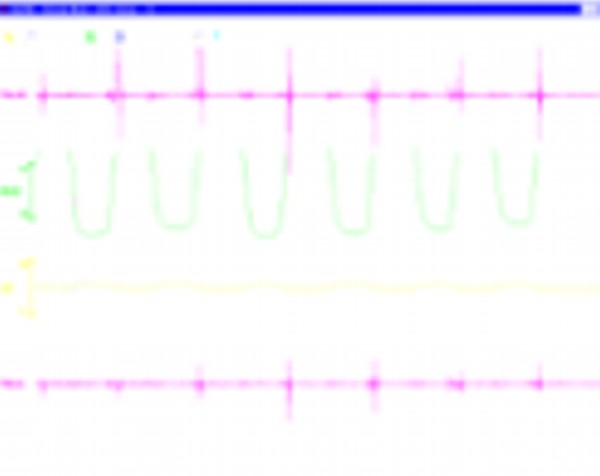

INTRODUCCIÓN El Bruxismo como entidad somática asociada al stress, responde a la mecánica de un Círculo Vicioso Patogénico, que Kawamura describiera hace ya muchos años. FACTOR DESENCADENANTE , que proveen las Interferencias a nivel dentario. En las entregas anteriores se desarrollaron las bases conceptuales de una OCLUSIÓN ORGÁNICA y los efectos de una mayor o menor Desoclusión según la variabilidad de los diferentes Factores Determinantes de la Oclusión. En síntesis; A-La obtención de una Oclusión en Relación Céntrica, nos permite devolver al sistema una elongación muscular fisiológica, sin acortamientos ni estiramientos musculares, sin las consecuentes estimulaciones de los husos neuro musculares, y; una situación estable de la A.T.M. con espacios articulares uniformes. B-El logro de una Guía Anterior que permita desocluir los sectores posteriores durante los movimientos excursivos, nos provée de una segunda y preponderante senda a transitar, que NO estimula por sus contactos excursivos la cincha Pterigo Maseterina, causante de las enormes destrucciones parafuncionales que es frecuente ver en bocas bruxómanas, y la axialización de las fuerzas sobre las piezas posteriores durante el cierre. C-Otorgando como consecuencia, Estabilidad a la tabla premolar-molar, simultaneidad en la recepción de fuerzas durante el cierre(A.T.M. y superficies oclusales). Obtendremos así una Oclusión estable y fisiológica, que no genere el FACTOR DESENCADENANTE del Bruxismo, siempre presente a nivel dentario. INTRODUCTION Bruxism as a somatic entity associated with stress responds to the mechanics of a Pathogenic Vicious Circle, described by Kawamura many years ago. Summarsing: A-Obtaining an oclusion in a Central Relation, allows us to return to the sistem a physiological muscular elongation, without muscular shotthenings or lenghthenings, without the following stimulations of the neuro-muscular huses and a stable situation of the Temporo Mandibular Joint with uniform articular spaces. B-The accomplishment of an Anterior Wide wich may allow disclusive the posterior sectors during the excursives movements, and the axial forces during the mandibular closure. C-Providing as a consecuence, axiality and stability to the posterior sections, responsible of the mandibular closure, through Sttopers, Equalitzers, A, B and C, to obtain a Oclusión Mutuamente Compartida: forces reception during mandibular closure (T.M.J. and Oclusal Surfaces) By this procedure, we should obtain a stable and physiological oclusion, that will not generate the chain link of factors that lead to Bruxism, always present at the dental level. MATERIALES Y MÉTODOS: La funciones articular y muscular, se analizaron mediante Bio Pack, en el pre, en el intra y en el post operatorio. Durante el diagnóstico, tratamiento y remontas, se utilizaron articuladores semi ajustables Wip Mix, totalmente ajustables Artex y arcos faciales correspondientes. El encerado de dianóstico se realizó, mediante la técnica de encerado progresivo de Peter K. Thomas. Los refuerzos a Perno Colado se llevaron a cabo con oro BIODENT YELLOW de ARGEDEN. Los tres juegos de provisionales utilizados, se hicieron con metacrilato termo curado. Las Restauraciones Periféricas Totales, fueron realizadas mediante porcelana CREATION de WILLY GUÉLLER, sobre oro BIODEN YELLOW de ARGEDEN. Los chequeos de los Contactos Interoclusales, se midieron con papeles de articular de 40 y 12 micrones, y mediante el analizador computarizado T-Scan. DESARROLLO Paciente varón de raza blanca, 42 años, complexión robusta y marcada hipertrofia maseterina. Fig.1 Fig.2 Fig.5 Se realiza un análisis pre-operatorio articular y muscular mediante Bio Pack, y oclusal mediante T-Scan, cuyos resultados muestran una evidente hiperactividad muscular en Temporal Anterior y Masetero Derechos, y contactos totalmente anómalos tanto en Oclusión Habitual como en Excéntricas. Fig. 6-7-8-9-10-11 Sensor de ruidos articulares Luego del primer intento de relajación mediante Laminillas de Long (Ref.6),Fig.12, registros y montaje, se observa la aparente presencia de una relación Borde a Borde, que luego se comprobaría que se trataba de una propulsión exagerada de su mandíbula en la búsqueda de contactos efectivos. Fig. 13-14 (Obsérvese el fenómeno de Patterson dado por la exclusiva guía de movimiento de la A.T.M. y la carencia de la Guía Anterior) Se procede a construir un JIG de LUCIA para lograr una desprogramación muscular adecuada, y se le indica permanecer con el colocado durante toda la noche anterior a la consulta, sin contactos dentarios posteriores. Aún en la duda, de que la obtenida sea una posición articular fisiológica, se procede a construir una Placa de Relajación sobre el último montaje obtenido, la que se ajusta cada dos días, y al cabo de tres semanas se procede a un tercer montaje obtenido de la nueva situación posicional. Fig.17-18 Se verifica entonces que estamos en realidad, ante una presunta CLASE II, después de tres métodos diferentes de relajación y transcurridos más de un més de múltiples sesiones para lograr una posición diagnóstica confiable a partir de donde comenzar a trabajar.(O.R.C.) Se adicionan entonces topes (montículos) en las caras oclusales de los primeros molares de la Placa de relajación, transformándola en una Férula Pivotante, de levísima altura, impidiendo el contacto de las demás piezas dentarias a fin de convertir la palanca en una de clase II (fisiológicamente el sistema se mueve según una palanca de clase III), y obtener de esa forma una descompresión de los espacios articulares, ya que si bien la A.T.M. era asintomática, estaba muy claro que la Dimensión Vertical Posterior se presentaba disminuida debido al exagerado desgaste de todos los sectores posteriores, cuya típica forma de «desgaste en olla», se verificaba en el análisis estático de los modelos.( Ref.7) En esa situación se remonta el modelo inferior puesto que el superior no modifica su posición espacial, y se realiza un Encerado de Progresivo Diagnóstico según PKT, previo análisis de los modelos mediante los analizadores de W.McHorris (Ref.8) Fig.18-19-20-21-22-23-24-25-26-27-28-29-30 Fig.18 Fig.22 Fig.23 (Obsérvese, que la Disclusión Propulsiva comienza en los rebordes mesiales del canino, sigue en los rebordes distales del lateral, y finaliza con los rebordes mesiales de los centrales.) Se realizan las endodoncias de toda la boca y se tallan los endodontos para la construcción de Pernos Muñones Colados de oro, los que se realizarán mediante técnica indirecta sobre los modelos :montados según los logros de todos los procedimientos de relajación. Se torna imprescindible la extracción de tres piezas dentarias, para la confección de la Guía Anterior, cuyo alineamiento hubiera sido imposible mediante técnicas reconstructivas ya que la posibilidad ortodóntica no era viable dadas las condiciones de desgaste. Fig.31-32-33-34-35-36-37 (Obsérvese, que desde la configuración de los Pernos Muñones Colados, se determina ya la Alineación Tridimensional que otorgaremos a la Rehabilitación Oral Integral del caso. Se monta entonces el primer juego de Provisionales de acrílico de termo curado, obtenido de la réplica del Encerado de Diagnóstico. Fig.38-39-40-41 (Obsérvese la presencia del ajuste periférico y las disclusiones, tan importantes en las provisorias como en las definitivas ya que del resultado de la etapa de provisionales, dependerá el éxito final.) Se ajustan las Unidades de Oclusión mediante Ajuste Oclusal (según técnica propuesta por la Cátedra de Operatoria Dental II y Prótesis de la Fac. de Odontología, Univ. Bs. As., Prof.Anibal Alonso.) Se deja actuando la nueva situación durante seis meses. Han transcurrido seis meses durante los cuales se instaló un nuevo juego de provisorios con las mismas características del anterior, y clinicamente no se observa hiperactividad muscular, perforaciones de los provisorios, molestias para desmenuzar los alimentos ni síntomas alguno en la A.T.M. NOS ENCONTRAMOS, CON UN SISTEMA EN PAZ A TODOS SUS NIVELES. Se procede entonces a la toma de impresiones definitivas, mediante la técnica de Impresión a Presión Masticatoria, para la confección de las restauraciones permanentes, y los metales se chequean mediante llaves de Duralay, para observar la situación análoga entre laboratorio y clínica.(Corroboración de la Oclusión en Relación Céntrica)Fig.42-43-44 Se prueban los metales y verifica su ajuste periférico. (Obsérvese que también en los metales sub porcelana se siguen las formas de las Preparaciones Funcionales, permitiendo de esta manera un perfecto bizcochado de la porcelana supra metal.) Realizada la Guía Anterior, Determinante Oclusal Primario y Anterior en el laboratorio, se prueban en boca sus características estáticas: Altura Funcional, Ángulo de la Disclusión y Punto de Acoplamiento, como así las dinámicas: Laterotrusión Derecha e Izquierda y Propulsión. En este estado las cosas, tenemos al sistema circunscripto tanto estática, como dinámicamente, por el gobierno de dos comandos, ya en Oclusión en Relación Céntrica, como en las Transtrusiones: Sabemos que todo lo que construyamos (tabla premolar-molar), entre estos dos comandos rectores del movimiento, partirán del mismo punto y volverán a el, transitando el recorrido impuesto por los mismos. Se construyen entonces en el laboratorio, las unidades de oclusión de premolares y molares, siendo las correspondientes a los cuatro últimos molares, con oclusal en oro, como un elemento de detención del cierre más poderoso que la porcelana.47-48-49-50-51 Se prueban en boca la Curva de Wilson, la Curva de Spee, la Alineación Tridimensional, los Espacios Uniformes Disclusivos, la Dirección de los Surcos de T, nT, y P, y los Puntos Interoclusales de Contacto. En laboratorio se retocan entonces los Puntos Interoclusales de contacto, acercando los mismo a la mejor posición ideal lograble, y luego de una nueva prueba en boca, se glacéan las piezas y se instalan en forma provisional durante 24 hs. Verificada la eficacia de las formas (FORMA=FUNCIÓN), se procede a constatar la eficiencia de la dinámica trayectorial y se cementan con cemento de fosfato mediante la técnica de cementado alterno. Fig.54-55-56-57-58-59-60-61-62-63-64-65-66-67-68-69. Fig.54 Fig.55 Curva de Wilson y Alineación Tridimensional en molares y premolares sup. Der. Fig.56 Fig.57 idem inferiores derechos Fig.58 Fig.59 Idem superiores izquierdos CONTACTOS INTEROCLUSALES SUPERIORES CONTACTOS INTEROCLUSALES INFERIORES Transcurrido un mes de instalada la Rehabilitación, se lleva a cabo un nuevo estudio, post operatorio con Bio Pack y Tscan. CONCLUSIONES : I-El paciente realiza una apertura bucal de 45mm sin forzamientos siguiendo una misma línea de apertura sin desvíos. II-Las disclusiones en laterotrusión se llevan a cabo mediante un recorrido lineal sobre los rebordes medios de ambos caninos superiores, creando un fenómeno de Luce con espacios uniformes en ambos lados. III-La disclusión en propulsión se manifiesta comenzando en los rebordes mesiales de ambos caninos, siguiendo por los rebordes distales de laterales y terminando en los rebordes mesiales de ambos centrales, dando lugar a un fenómeno de Christensen con espacios uniformes de ambos lados. IV-Los contactos interoclusales son suficientes, simultáneos y tripódicos logrando la estabilidad en ambos planos del espacio tanto de las piezas individuales como en conjunto, sin contactos deflectivos. V-Realizado un nuevo montaje de la boca terminada, corroboramos como estable la Oclusión en Relación Céntrica. VI-No existen movilidades dentarias y los tejidos periodontales y gingivales se encuentran estabilizados. VII-No existen ruidos articulares. VIII-El resultado post operatorio Bio Pack de la dinámica mandibular, muestra una sustancial mejora de los movimientos en los tres planos del espacio. IX-Electromiográficamente, se observan contracciones musculares dentro de los rangos de normalidad, persistiendo un rango ligeramente elevado en temporal anterior y masetero del lado derecho, presumiblemente debido a la hipertrofia que dicho paciente traía, y mostraba en el estudio pre-operatorio. COMPARACIONES PRE, INTRA Y POST OPERATORIAS Sonografía de la ATM: Tanto en el examen pre como post operatorio no se observaron ruidos de ningún tipo, coincidiendo con la exploración clínica pre auricular e intra auricular. Electromiografía: La electromiografía en reposo, muestra bien a las claras la presencia de músculos hipertónicos durante el estudio pre operatorio, fundamentalmente del grupo Temporal Anterior y Digástricos, estando el Masetero izquierdo ligeramente por encima de su rango normal como así también ambos Esternocleidomastoideos. Durante el estudio post operatorio, se verifica el estado tónico de todos los grupos musculares, persistiendo una ligera hipertonicidad de rango levemente por encima de lo fisiológico, en el Temporal Anterior Derecho y Digástrico Derecho. PRE OPERATORIO POST OPERATORIO Temporal Ant. Der. 4.4 2.8 Temporal Ant. Izq. 6.2 1.1 Masetero Der. 1.2 0.5 Masetero Izq. 1.5 0.8 Est.Cleid.Mast. Der. 1.6 0.3 Est.Cleid.Mast. Izq. 2.1 0.2 Digástrico Der. 1.7 2.9 Digástrico Izq. 1.6 0.7 (La unidad de medida utilizada es el microvoltio ) Dinámica mandibular: Durante el Pre Operatorio, en el Plano Sagital, tanto la Apertura como el Cierre lento, se manifiesta mediante una acentuada tendencia a propulsar la mandibula. Durante el Post Operatorio, la tendencia hacia la derecha de estos dos últimos planos se mantiene, mientras que en Plano Sagital, la propulsión inicial no se produce, asemejándose el movimiento a la primera fase del Bicuspóide de Posselt. El Análisis de la Dinámica realizado durante la Masticación (chicle), nos muestra en el Plano Sagital, la propulsión mencionada durante la apertura y cierre lentos durante el estudio Pre Operatorio, se aproxima a la normalidad durante el Intra Operatorio (2º juego de provisionales), y se vuelve a manifestar propulsivo, en el Post Operatorio. En cuanto al Plano Frontal, durante el Pre Op. , ofrece un Ciclo Masticatorio(recordar la forma de «gota de agua») para el lado izq., con componentes derechos e izquierdos alternos, que se aproximan paulatinamente al Ciclo Masticatorio Normal, durante el Intra y Post Operatorio. El Plano horizontal, confirma las afirmaciones anteriores durante los tres períodos de estudio. ANÁLISIS MEDIANTE TSCAN 1-Bio Pack Bio Research Associates,Inc Distrib.UEDA S.A. 2-Wip Mix-Artex 3-Au:89% / Pt:6% /Elementos complementarios:5% 4-Idem ref.3 5-Tscan TekSkan,Inc Distrib.UEDA S.A. 6-Mc Horris.Cátedra de Operatoria Dental II y Prótesis. 7-Alonso.Cátedra de Operatoria Dental II y prótesis. 8-Mc.Horris. Analizadores de Guía Anterior. BIBLIOGRAFÍA: 1-Esquemas de las dos primeras entregas, tomadas del libro:»Oclusión Orgánica…un camino hacia la Rehabilitación Oral» 2-Oclusión y Diagnóstico en Rehabilitación Oral. 3-Anatomia Odontológica. 4-A contribution to the study of the movementes of the mandible. 5-Celenza F.W, Nadeskin J.F.,Oclusión.Situación actual. 6-D´Amico 7-Dawson P.E. 8-Huffman -Regenos. 9-Hobo S.-Takayama H.A. 10-Lucia V.O 11-Mc Horris. 12-Mc Horris. 13-Posselt U. 14-Stuart C. 15-Vartan Veshnilian AGRADECIMIENTOS: La Rehabilitación Oral, especialidad donde se hace imprescindible el manejo y concurrencia de todas las especialidades dentales en su desarrollo más depurado, no tendría razón de ser, sin la más estrecha colaboración de una técnica para- médica con detalles de excelencia. Sr. Pedro Colomina: muchas gracias. Pedro Colomina. – Titulado especialista en prótesis dental en la escuela Ramon y Cajal de Barcelona 1988

Al cabo de los mismos se realiza una nueva comprobación del estado articular y muscular mediante Bio Pack y un chequeo oclusal mediante T-Scan, donde se observan una evidente mejoría de la musculatura comprometida, de la dinámica mandibular, de la apertura bucal, de los contactos simultáneos de la Oclusión en Relación Céntrica como así de las Excéntricas, y un manifiesto control masticatorio por parte del paciente.

Pre Operatoria Post Operatoria

Pre Operatoria Post Operatoria

Pre Operatoria Post Operatoria

Pre Operatoria Intra Operatoria

Pre Operatorio Post Operatorio

InmediatoLa evidencia de la falta de contactos, en el Pre Operatorio, se ve sustituida por la uniforme distribución de los mismos en el Post Operatorio, como así también el centrado de la línea resultante de fuerzas.